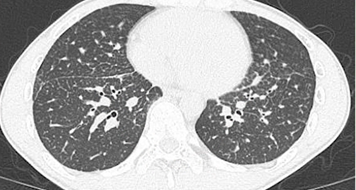

CTでは粒状影が多発しています。気管支鏡検査(TBLB)施行し、サルコイドーシスの確定診断です。鑑別にサルコイドーシスを挙げていると、あらかじめACEやリゾチームなどを出せるようになります。